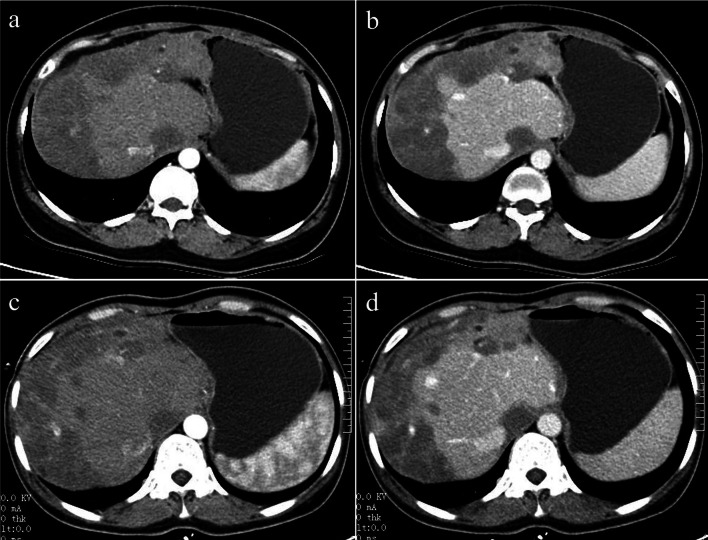

The diffuse type was observed in 8 patients (8/20, 40%). CT features included diffuse low-density lesions with minimal residual areas of normal liver parenchyma, multiple nodules and confluent masses with strip‑like enhancement located at the edge of the liver. Coalescent lesions were detected in most of the cases (7/8, 87.5%). Changes similar to those in liver cirrhosis were detected in 2 patients, such as liver morphological changes, proportion imbalance, and widened hepatic hilar and hepatic fissures (Fig. 4). Multiple lesions displayed slight or ring-like enhancement in the arterial phase and gradual homogeneous or heterogeneous enhancement in the portal phase. One patient showed involvement of lymph nodes; both the peritoneum and lung were invaded in another patient (Fig. 5). Stenosis or occlusion of the branches of the portal and hepatic veins was also detected in 2 patients (Fig. 6).

Fig. 4.

A 40-year-old female with diffuse nodular type HEH. Axial arterial and portal phase CT images (a, b) show multiple, diffuse nodules that lack obvious enhancement and confluent masses with strip-like enhancement located at the subcapsular region of the liver, accompanied by liver morphological changes and proportion imbalance. On follow-up CT performed 18 months later without any treatment, axial arterial and portal phase images (c, d) show no obvious changes in the lesions